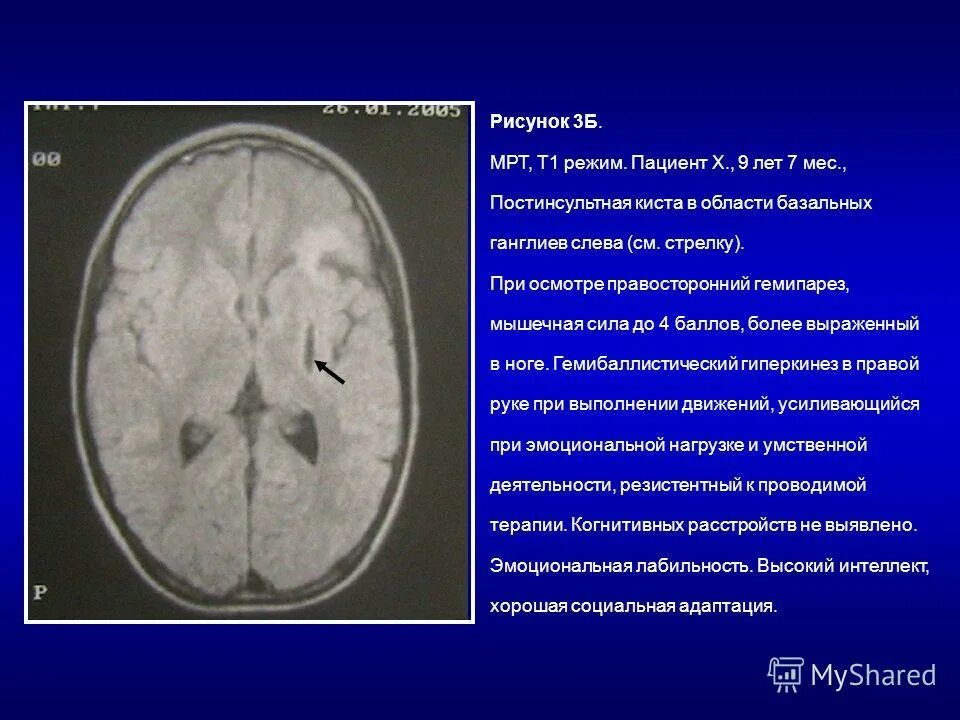

Киста базальных ядер слева